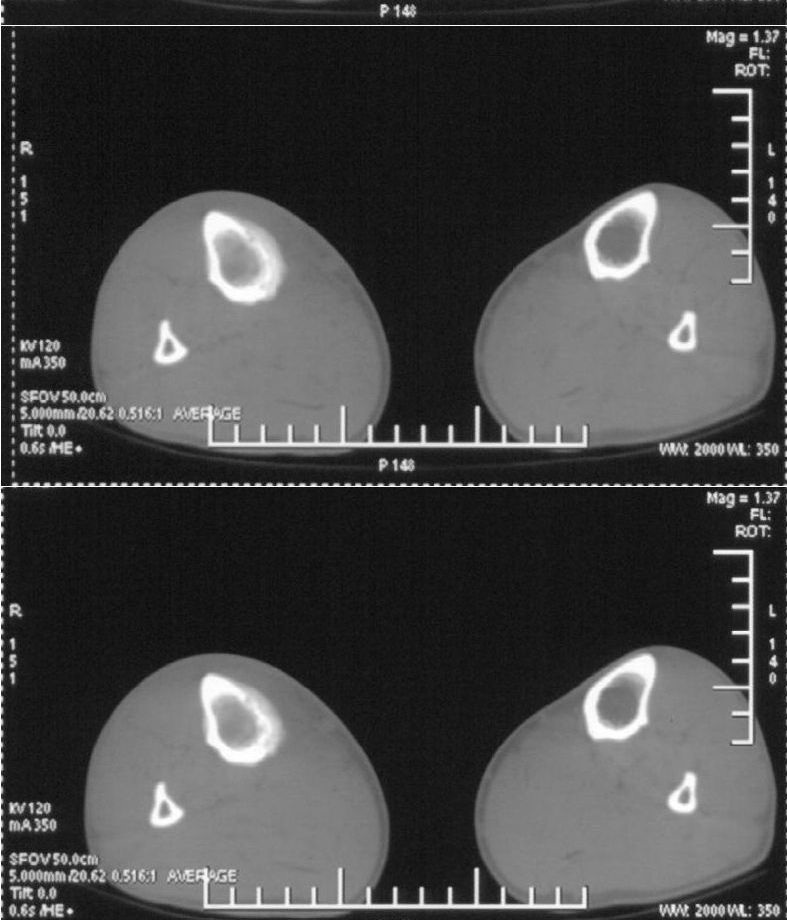

男,42岁。4个月前钢筋钝伤右侧小腿部,当时因无明显外伤,未引起重视。一周后因受伤腿部疼痛,发现肿胀,随后到当地医院进行检查(2008年4月16日)。因未发现骨质异常未引起重视,仅仅进行口服抗生素治疗处理。经过一段时间治疗但未见明显治疗效果在5月29日又进行x线检查,发现有胫骨密度上段密度增高,又进行抗炎治疗,仍未见效果。又在7月3日进行x线检查,仍然报告有胫骨上端密度增高,并建议ct检查。以下是相关检查结果:

髓腔密度呈絮状增高,胫骨上端内侧可见层状骨膜反应,考虑骨髓炎.

髓腔密度呈絮状增高,胫骨上端内侧可见层状骨膜反应,肌间隙模糊,考虑骨髓炎.